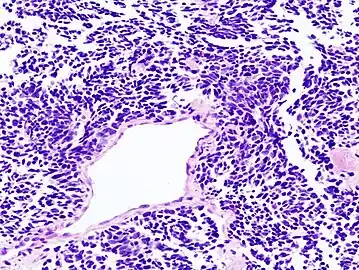

Histopathologic image of small-cell carcinoma of the lung. CT-guided core needle biopsy.

Small-cell carcinoma is an undifferentiated neoplasm composed of primitive-appearing cells. As the name implies, the cells in small-cell carcinomas are smaller than normal cells, and barely have room for any cytoplasm. Some researchers identify this as a failure in the mechanism that controls the size of the cells.[43]